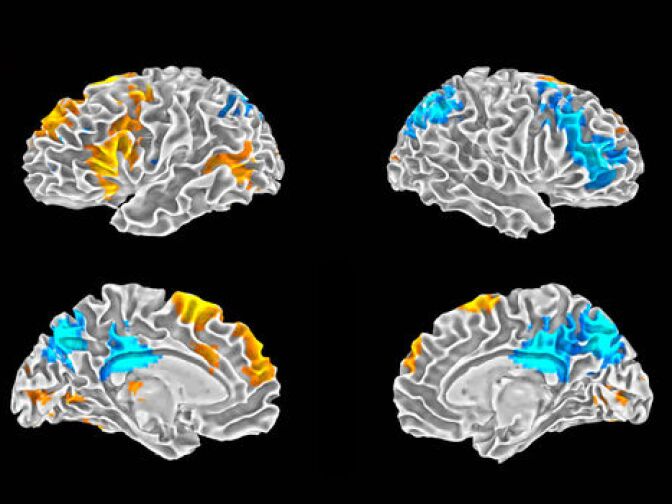

In both conditions, Braun explained, “we acquired images related to brain activity, and this is using an fMRI method,” (functional MRI) “and that tells us what areas of the brain are more or less active and we can get a picture of what the brain is doing, specifically during freestyle rapping.”

Braun examined the brain images of the rappers while they were freestyling rhymes. He found an interesting pattern of activity in the prefrontal cortex. Basically, the areas associated with self-generated and self-motivated behavior were active but the areas that monitor or censor behavior were de-activated. So while there is an aspect of the brain that is energized by using improvisational skills, there is much less self-censoring at play.

Researcher Allen Braun explained that as this self-censoring area of the brain is deactivated, the “artists... are able to produce these improvisatory associations, surprising connections between words and rhythmic patterns and so on, that are produced really outside of conscious awareness.”